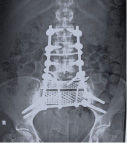

Grafide sakrumda orta hat yerleşimli, belirsiz sınırlı, litik bir kitle görülür. Düz grafide görüntü almak çok zordur. MRI incelemesi, tümörün tüm uzanımını, öndeki rektum, mesane, damarlar ve özellikle sinir kökleri ile ilişkisini gösterir. BT’de kemikteki destrüksiyon en iyi şekilde görülür. Ayırıcı tanıda dev hücreli tümör, anevrizmal kemik kisti, kondrosarkom dikkate alınmalıdır.

Kordomada kemoterapi ve radyoterapinin etkisi yoktur, buna karşın lokal tekrarlama eğilimi çok yüksektir. Yetersiz cerrahi yapıldığında lokal nüks gelişir. Esas tedavisi cerrahidir. İmkan dahilinde geniş rezeksiyonla çıkartılmalıdır. Teknik olarak tam çıkartılamaz ise radyoterapi (RT) uygulanmalıdır. Geniş rezeksiyon yapıldığında 5 yıl yaşam şansı %73, 10 yıl yaşam beklentisi %58’dir. Hastaların %30’unda metastaz görülür.